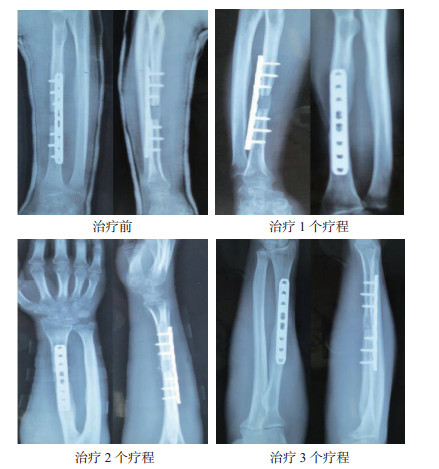

2 结果治疗前患者骨折断端处可见有清晰的骨折线,治疗1个疗程患者骨折断端骨痂生成,治疗2个疗程患者骨折断端处骨折线模糊,治疗3个疗程患者骨折断端处有大量的骨痂生成,骨折线消失,并形成骨链接。见图 1。

| 图 1 骨折延迟愈合患者治疗前后骨折部位变化 |